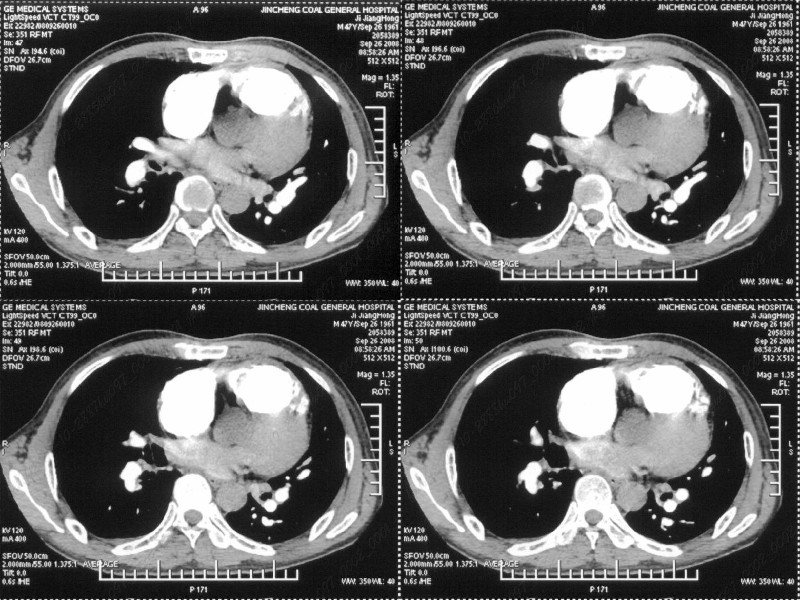

男性,47岁。胸部不适一年,ct检查发现右胸膜下结节。http://www.radida.com/bbs/forum.php?mod=viewthread&tid=46094

图像很清,资料很全。工作做的很细,向您学习!观阁下的强化图像发现,您们强化后扫描时间挺早,延迟时间大约在16—18秒之间吧。估计目的是为了观察肺动脉及分支的情况。但现有的资料并不能提示动脉栓塞改变。建议楼主可在机器上仔细观察,或许会有异常发现。另外,个人感觉右侧应为肺内结节而非胸膜结节。考虑肺内良性小结节,炎性假瘤可能性大。

病灶周围似有纤维化征像,增强明显强化,但中央可见点状低强化区,考虑慢性病变可能如炎性假瘤等,病灶边缘部分毛糙有切迹,双侧胸腔少量积液影,不除外恶性

结节未见明显强化,局部胸膜增后粘连,内缘纹理影增重伴小围星灶,局部胸膜下小三角状实变影,尖端见纤维索牵扯征,综合考虑炎性病变,有增殖表现,不出外tb灶

小结节的周围似乎与斜裂的走行有关,边缘分界不很清楚,与侧胸膜关系密切,有轻度强化,不能除外恶性,建议密切观察。

汇报临床诊断:右肺动脉分枝栓塞

右肺静脉充盈缺损,左心房体积小,右肺动脉远端动脉充盈缺损,右肺血管影细小,考虑;右肺动脉远端栓塞.